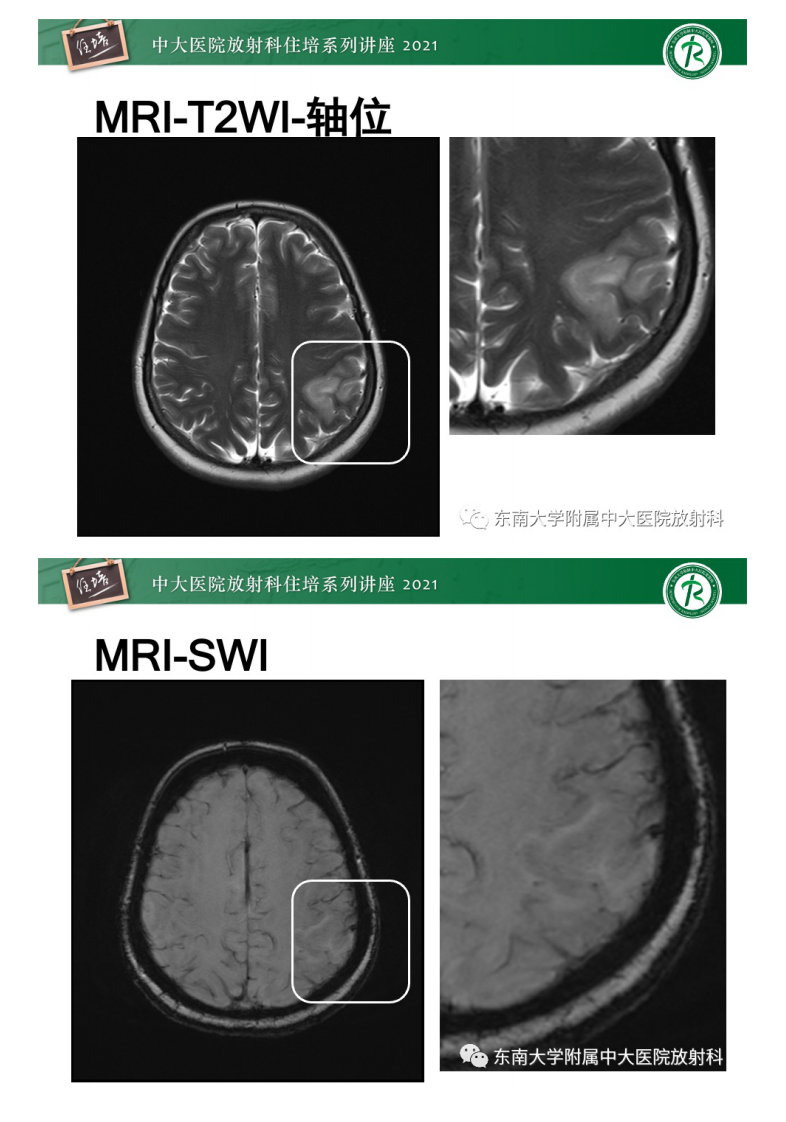

20210506_1【中大放射住培系列讲座】静脉性脑梗死的诊断思路.pdf